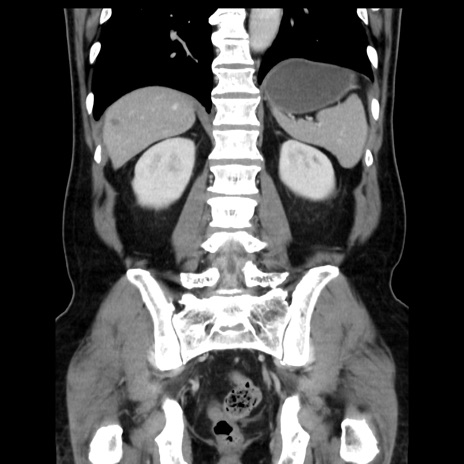

横断像

【症例】 70歳代男性

【主訴】 腹痛、嘔吐

【現病歴】 約1ヶ月前より間欠的に腹痛と嘔吐あり、当院消化器内科を受診したところCTで多発する肝臓のLDAを指摘され、精査中であった。以降は消化器症状は安定していたが、2日前より嘔気と腹痛があり、同日より排便・排ガスが消失した。改善認めず、 本日、救急外来を受診した。

【身体所見】意識清明・会話良好、BT 36.3℃、BP 127/80mmHg、 P 80bpm、腹部:膨満あり、平坦・軟、上腹部正中および下腹部正中に圧痛あり、反跳痛なし、筋性防御なし。

【データ】WBC 7200、CRP 0.77